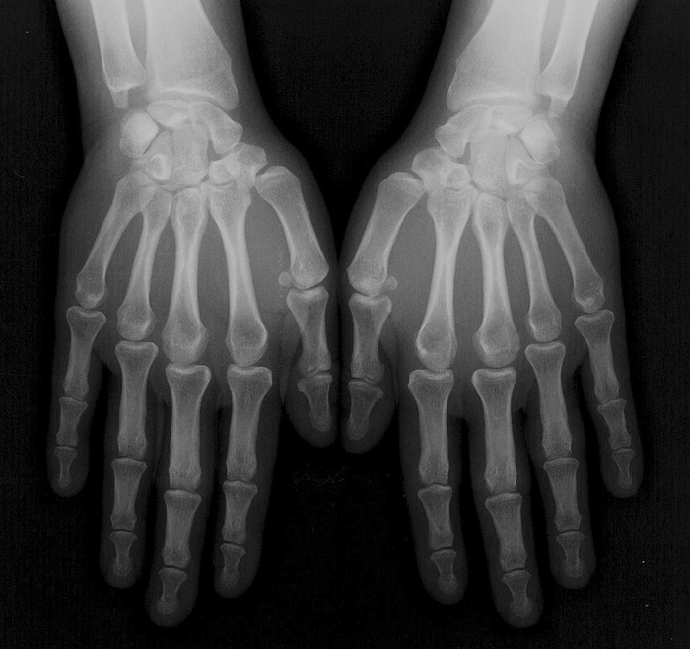

Cette étude sur l’arthrose des doigts est la première en France de cette envergure.

Cette recherche a pour objectif de déterminer des signes cliniques, biologiques et radiographiques permettant de prévoir la progression de l’arthrose digitale (également appelée arthrose des mains).

A terme, elle permettrait d’avoir une meilleure connaissance de l’évolution de l’arthrose digitale.